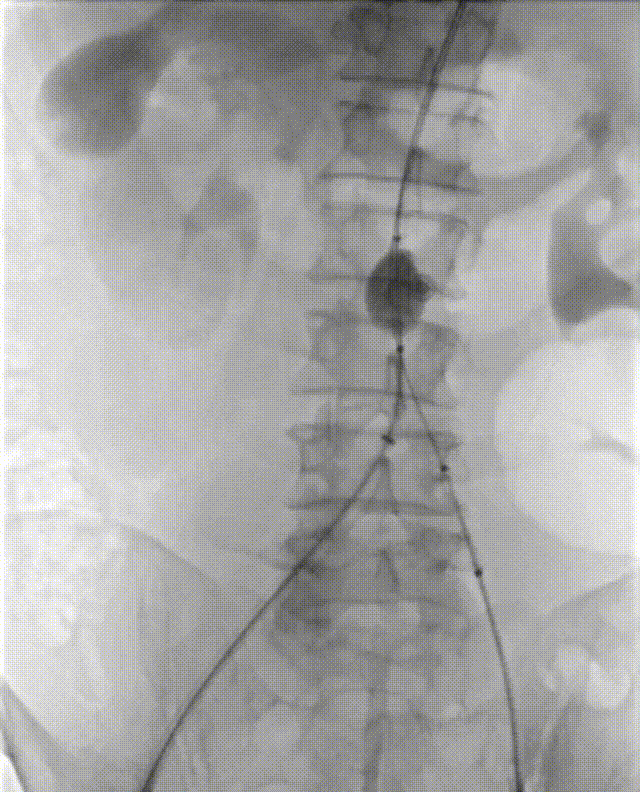

2. 经左侧股动脉入路,建立至降主动脉的输送通道,交换导丝,送入MOB球囊,将球囊位置推送至肾动脉以下,充盈球囊,阻断血流。

4. 穿刺左桡动脉,经左锁骨下动脉通过,输送导丝及椎管,输送至球囊近端附近,造影确认肾动脉位置。